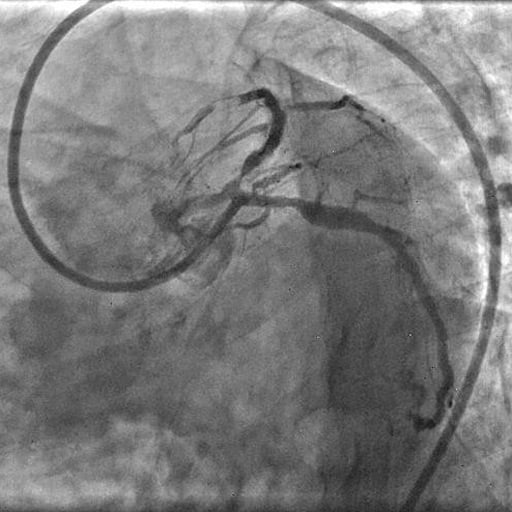

Picture 4: Check angiogram demonstrating thrombus embolisation.

The patient was urgently transferred back to the catheterisation laboratory for revascularisation. A check angiogram prompted reconsideration of the initial strategy (rotational atherectomy vs cutting balloon), as distal thrombus embolisation was noted.

The differential diagnosis included acute thrombosis and iatrogenic dissection in the setting of heavy calcification.